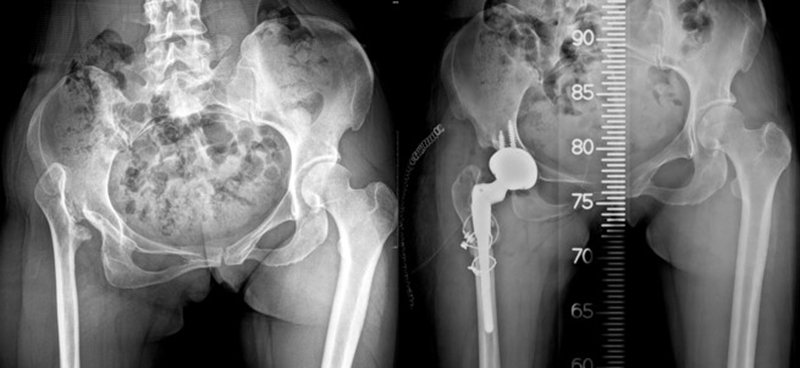

全髋关节置换术具有优异的疼痛缓解、稳定可靠的固定及良好的功能恢复和长期随访结果等优点,常用于治疗各种晚期髋关节疾病。在全髋关节置换中,畸形常发生在股骨侧,非常难处理,是髋关节置换中难题之一。

导致股骨近端畸形的原因主要有原发型和继发型两大类。原发型多为发育异常所致(DDH)、代谢性骨病、强直性脊柱炎引起;继发型主要为手术所致,包括股骨近端截骨术、股骨近端骨折内固定术、全髋或半髋置换,其他因素如感染、创伤畸形愈合等。

目前临床上对于股骨近端畸形的处理,仍是关节外科的难题之一,在处理时常面临以下挑战:①费时、费力、费脑子;②手术复杂,时间长,并发症高;③特殊假体;④多种畸形同时矫正不易;⑤截骨重建困难、骨折愈合难;⑥股骨近端开口位置错误,股骨穿孔或骨折,假体柄非中心安置;⑦臀中肌张力不易调整;⑧并发症:撞击、关节不稳、反复脱位、远期松动等。